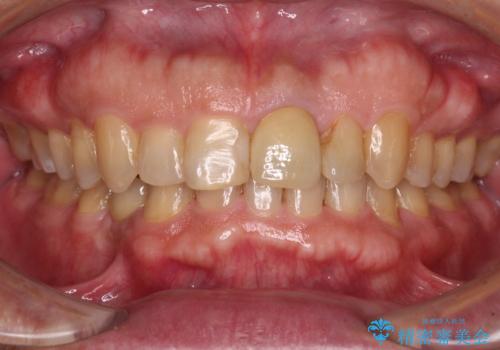

インビザラインによる治療を希望されたため、左側のスペースは閉じ、右側はスペースをより拡大し、インプラント補綴を行うこととしました。

咬合力が強く、インビザラインのみではディープバイトを改善することができず、半年間ほどワイヤー装置による矯正治療を行いました。

インプラントの埋入は矯正治療中に行い、矯正治療後はインプラント上補綴および、前歯のセラミック治療を行いました。